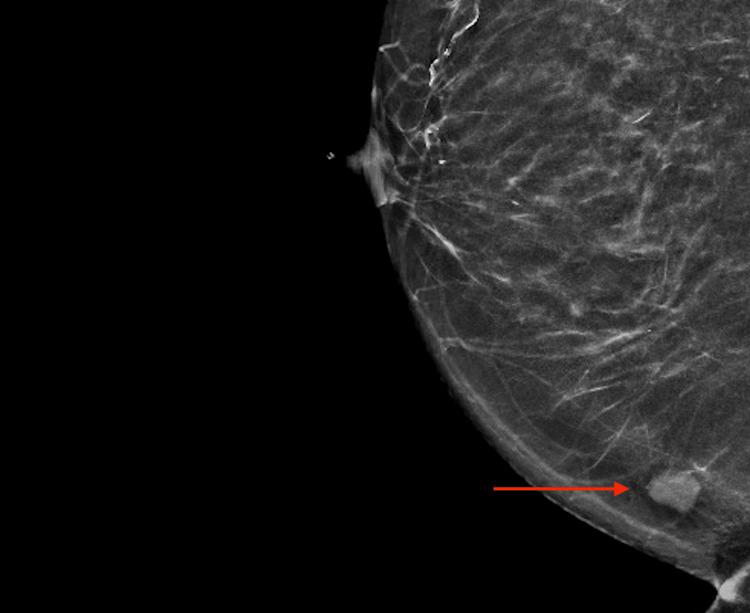

Gastrointestinal stromal tumor (GIST) is one of the most common spindle cell neoplasms of the alimentary system, and can arise anywhere along the gastrointestinal tract (GI). Its incidence rate is up to 22 cases per million, with a minor geographic variation. GIST is thought to originate from interstitial cell of Cajal, and its pathogenesis is related to molecular defects, such as KIT receptor tyrosine kinase or platelet-derived growth receptor alpha gene activation. While the majority of GISTs are known to show a benign disease course, metastases of high-grade forms to different organ systems have been seldom reported. We present a case with an unprecedented metastasis of GIST to the breast. The patient is a 62-year-old female with a history of the primary resection of GIST from the small intestine. Her disease course was initially complicated by multiple metastases, solely localized to the liver for which she had a living-donor liver transplant. The tumor harbored both KIT exon 11 and exon 17 mutation. Fourteen months post-transplant, the patient was found to have metastatic GIST on her breast biopsy. GIST metastasis to the breast is extremely rare. A consideration of this spindle cell neoplasm as a differential is recommended when clinical suspicion arises. The pathophysiology, current diagnostic tool, grading system, and treatment of this tumor are discussed.

胃肠道间质瘤(GIST)是消化系统最常见的梭形细胞瘤之一,可发生于胃肠道(GI)的任何部位。其发病率高达每百万人口22例,地域差异较小。GIST被认为起源于 Cajal 间质细胞,其发病机制与分子缺陷有关,如 KIT 受体酪氨酸激酶或血小板衍生生长因子受体α基因激活。虽然大多数GIST表现为良性病程,但高级别GIST转移至不同器官系统的报道很少。我们报告一例GIST罕见转移至乳腺的病例。患者为62岁女性,有小肠原发性GIST切除病史。其病程最初因多处转移而复杂化,仅局限于肝脏,为此她接受了活体供肝移植。肿瘤同时存在KIT外显子11和外显子17突变。移植后14个月,患者乳腺活检发现转移性GIST。GIST转移至乳腺极为罕见。当临床出现怀疑时,建议将这种梭形细胞瘤作为鉴别诊断的考虑对象。本文讨论了该肿瘤的病理生理学、当前诊断工具、分级系统及治疗方法。